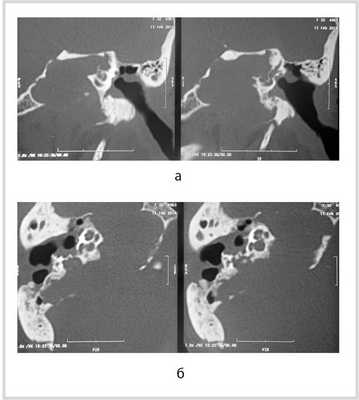

Рис. 1. КТ височных костей пациентки М. а — коронарная проекция: деструктивная полость в пирамиде височной кости, заполненная субстратом неоднородной плотности, капсула лабиринта значительно разрушена на уровне базального и апикального завитков улитки, латерального и верхнего полукружных каналов; б — аксиальная проекция: деструктивная полость с разрушением задней грани пирамиды, передневерхней и нижней поверхности.

По результатам МРТ головного мозга правая пирамида височной кости деформирована, увеличена в объеме, выполнена субстратом размером до 5,5—2,8—3 см, распространяющимся на область внутреннего слухового прохода, заднего полукружного канала, медиальные отделы барабанной полости, сосцевидный отросток. Описанный субстрат изо-гипоинтенсивен в режиме Т1, гиперинтенсивен — в Т2 и non-EPI DWI (рис. 2). Заключение: признаки рецидива холестеатомы с деструктивными изменениями структур внутреннего и среднего уха на фоне хронических воспалительных изменений.

Рис. 2. Магнитно-резонансная томография головного мозга пациентки М. Деформированная, увеличенная в объеме пирамида височной кости выполнена мягкотканым субстратом.